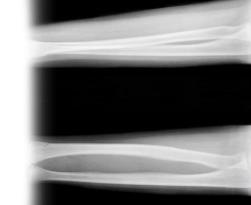

Рентгенография локтевой и лучевой кости – важный метод прицельного исследования, который позволяет оценить состояние костей предплечья.

Диагностическая услуга выполняется в двух проекциях.

Рентген позволяет исключить патологию костей предплечья костно-травматологического, опухолевого и воспалительного генеза.